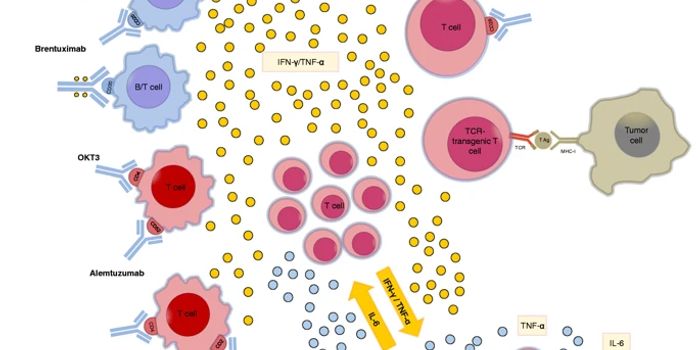

APR 25, 2024Drug Discovery & DevelopmentBy designing a new cytokine receptor, researchers at Keio University in Tokyo have elevate the efficacy and safety of CA ...